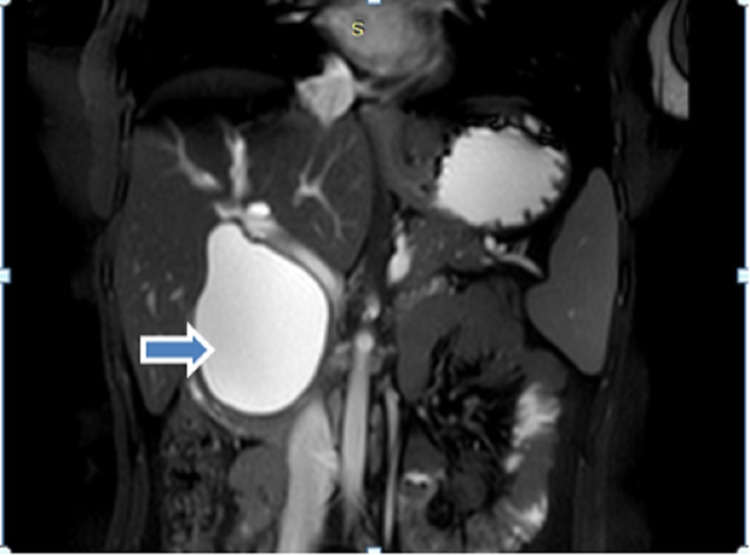

A 38-year-old female presented to our hospital with complaints of pain in the upper abdomen for six months with increased intensity since last one month which was not related to food intake and was not radiating to the back. She had no symptoms of jaundice and fever. On abdominal examination, there was no palpable mass or other significant findings. There were no abnormal findings in the laboratory test. USG abdomen revealed cystic dilation of CBD with the normal gall bladder. Further evaluation with magnetic resonance cholangiopancreatography (MRCP) abdomen revealed dilated cystic structure seen in the region of CBD measuring about 55 mm with smooth distal tapering suggestive of CDC type 1a according to Todani classification (Figure 1).